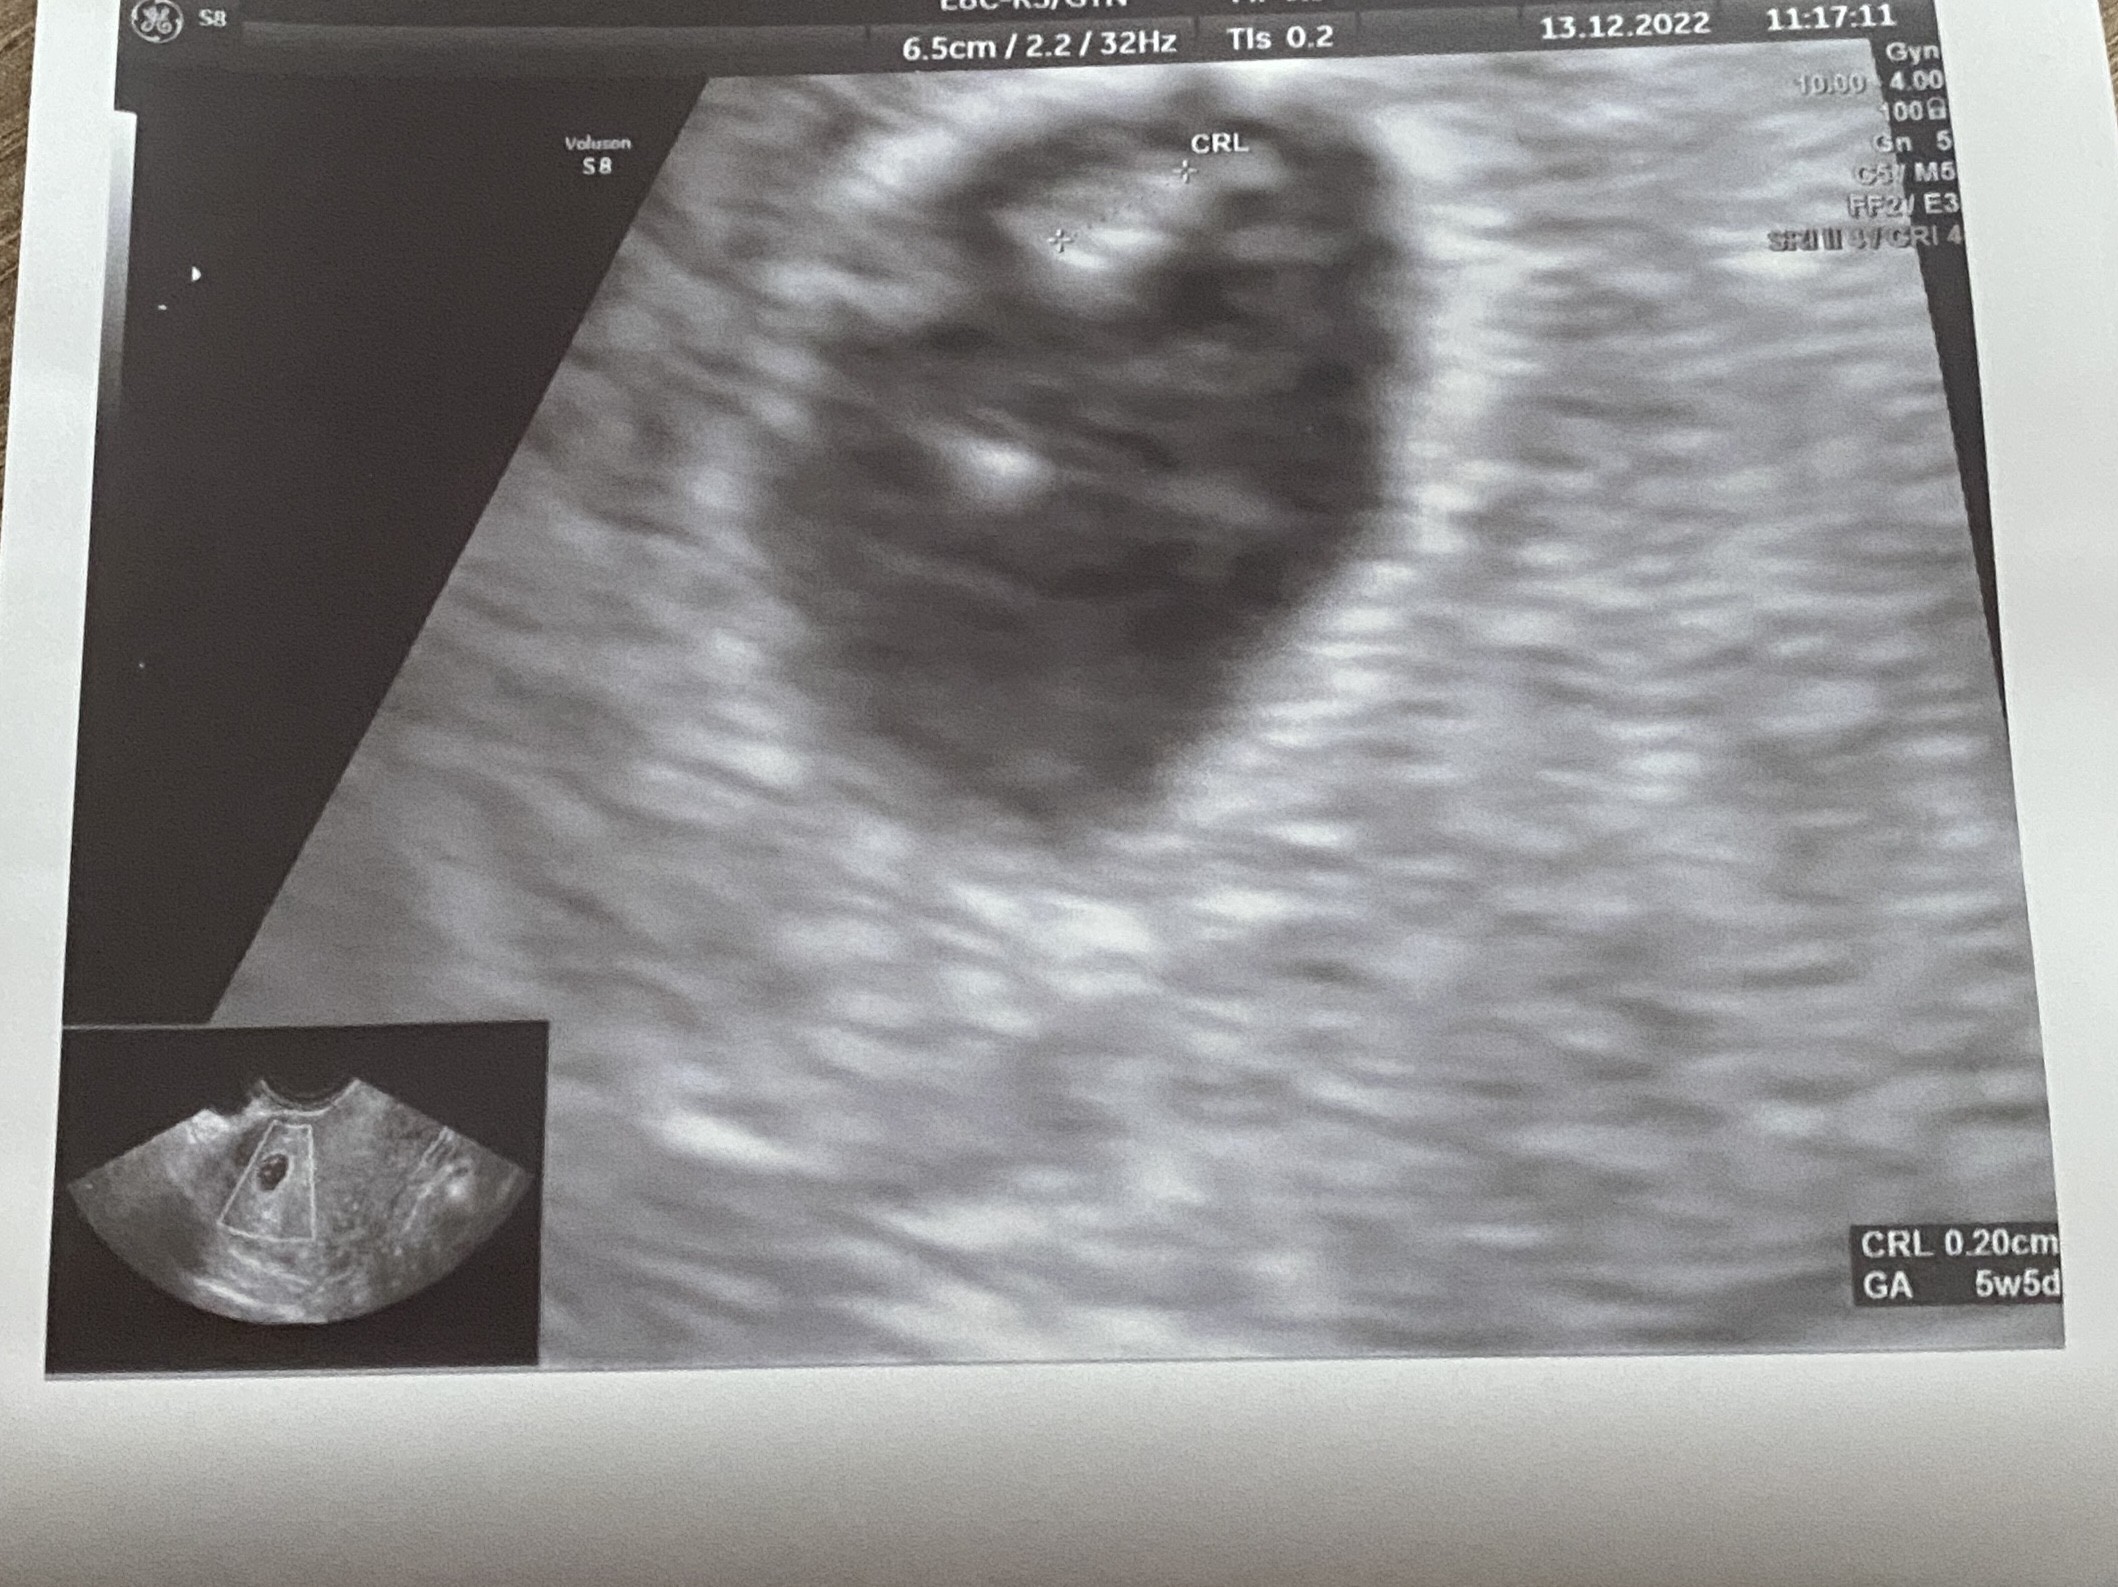

U mnie to wyglada tak, według lekarza byłam 5+5, według om 6+0. Zarodek 2 mm tylko.

Załączniki

• F2437194-ED0C-4E25-9150-EEA9FC45F0F2.jpeg

F2437194-ED0C-4E25-9150-EEA9FC45F0F2.jpeg

648,4 KB · Wyświetleń: 71